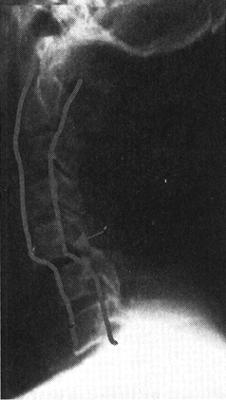

脊髓创伤慢性期改变也称创伤后脊髓病,可出现在急性创伤手术或保守治疗后。创伤后脊髓病的病变按发病率高低依次为:创伤性椎管狭窄、脊髓软化、创伤后脊髓空洞症、创伤性脊膜囊肿、脊髓萎缩和瘘管形成等。

(1)创伤后椎管狭窄:脊柱创伤经手术矫形或保守治疗后,都可发生椎管狭窄,主要原因是骨质增生、椎间盘破裂、韧带断裂致椎体不稳、瘢痕的粘连和增生等。这些继发性的改变可压迫脊髓和神经根引发神经功能障碍。MRI可清楚显示椎管狭窄的部位和受压的脊髓和神经根。

(2)脊髓软化和空洞:脊髓软化在创伤后48h后即可开始,是由于脊髓内出血、水肿引起的炎症性反应和肉芽组织对创伤组织的清除所致,可能同时伴有胶质细胞的增生和吞噬细胞功能的增强使脊髓脂质崩解、软化和液化,并被吞噬细胞吞噬和转移,最终形成脊髓软化和空洞形成。MRI可显示这种病理改变。脊髓软化灶在T1WI表现为低信号,在T2WI为高信号,增强扫描无强化。脊髓空洞在T1WI和T2WI信号等同于脑脊液信号,而边缘更加清晰(图7-19)。脊髓软化和空洞是神经系统症状恶化的主要原因。脊髓空洞引流是治疗的重要手段,因而正确的诊断和定位十分重要。大约9%~20%的脊髓损伤病人可出现脊髓空洞症。

X线脊髓造影可显示蛛网膜炎和受伤节段的粘连以及脊髓病灶的大小。脊髓囊肿的诊断不应基于局部脊髓的扩大,因为许多有囊肿的脊髓大小可正常。常见的有囊肿的正常大小的脊髓或萎缩的脊髓位于脊髓背侧或在受伤节段以上。脊髓空洞平均长约6cm,亦可小至0.5cm或占满整个脊髓腔。正常脊髓直径的改变或不同部位的脊髓萎缩有助于脊髓空洞的诊断。50%以上有瘘管的病人有随位置变化的脊髓大小改变,仰卧位时脊髓的缩小是最具有特征性的改变。脊髓大小的位置改变在MRI和CTM上比X线脊髓造影更易于显示。